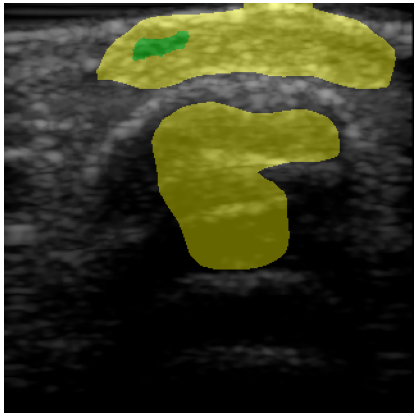

For quantitative evaluation of the network, we calculated precision, recall and the Dice score, also known as F1 score, of the network prediction compared to the GT annotation. Results are also visualized to compare GT with the network prediction. True positive (TP) pixels are colored green, false positives (FP) are colored yellow, false negatives (FN) are colored red and true negative (TN) areas are transparent.

Figure 2: (a-d) Four representative US wound images. (e-h) Visualization of corresponding segmentation predictions for FCN. Green indicates correct matches, red and yellow indicate missed (false negative) and oversegmented (false positive) areas, respectively.

Table 2 shows the quantitative evaluation of the algorithms. U-Net and FCN both achieve a Dice score of 0.340.340.34 compared to pre-trained ResNet-U-Net which has a Dice score of 0.270.270.27. Visualizations of the segmentation results for FCN are shown in Figure 2, where (a-d) are the original inputs, and (e-h) the corresponding color-coded outcomes. In general, the performance is promising for a number of cases, although we see a high FP rate (d,h) for others. Table 3 shows the ratio of m¯rsubscript¯𝑚𝑟\overline{m}_{r} for different wound regions compared to m¯wsubscript¯𝑚𝑤\overline{m}_{w} of the whole wound area. In the wound center, the US values are lower (ratio: 0.89 ±plus-or-minus\pm 0.11), compared to the wound borders (ratio: 1.47 ±plus-or-minus\pm 0.37).

In this work, we showed a proof-of-concept for a non-invasive imaging technique paired with machine learning. We performed initial experiments for automatic segmentation of US wound images with deep learning which show an Dice score of 0.340.340.34 for both U-Net and FCN and 0.270.270.27 for ResNet-U-Net. The segmentation results strongly depend on the quality of the scan and the specific wound type. Quantitative results can still be improved but the visual examination of the results indicates applicability of the proposed setup. For images illustrated in Figure 2(e-g), the segmentation is very good. However, the network misclassifies the region beneath the hyperechoic bone surface (image h) as this region therefore appears dark and similar in intensity to the wound region.